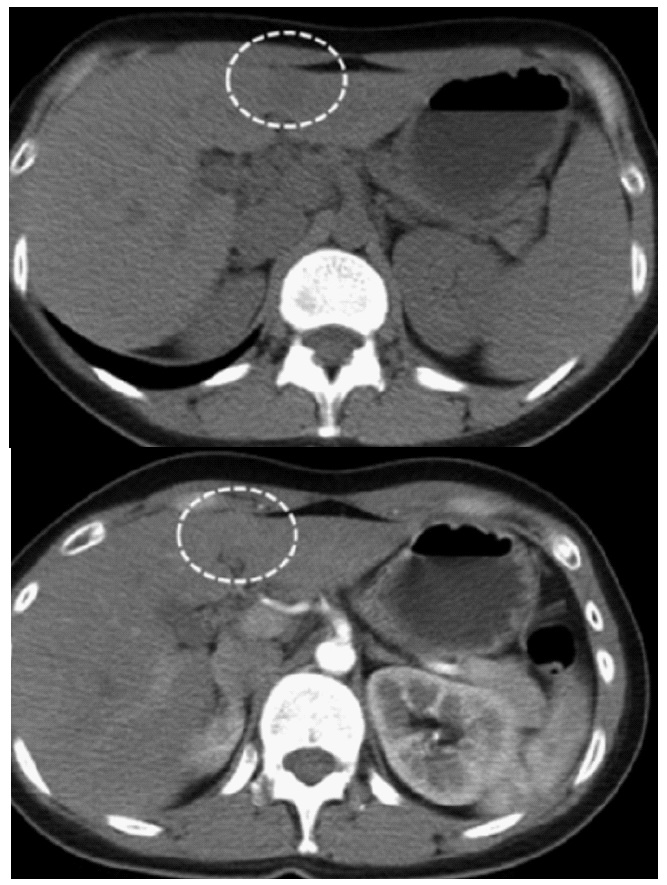

The CT scanner revealed a 2.7 cm hypodense tumor in left lateral segment, with hyperenhancement in arterial phase and wash-out in veinous phase (Figure 1). He was diagnosed with hepatocellular carcinoma and underwent laparoscopic left lateral segmentectomy. The tumor was located in the central of segment 3. The spicimen was shown in (Figure 2). The postoperative course was uneventful, and the patient was discharged on postoperative day 5.

Hepatocellular carcinoma is the most common primary liver cancer in the world, and in our country. Our patient hospitalized with HCC-like characteristics. He had a background of cirrhosis with chronic HBV infection. The radiologic features were also mimic HCC, with wash-out features. No further biopsy was necessary, the patient had the criteria for a diagnosis of HCC according to the American Association for the Study of Liver Diseases Practice Guidelines [4]. The laparoscopic liver resection indication was reasonable at the time of clinical diagnosis. The final diagnosis of LELC was solely depended on pathology.